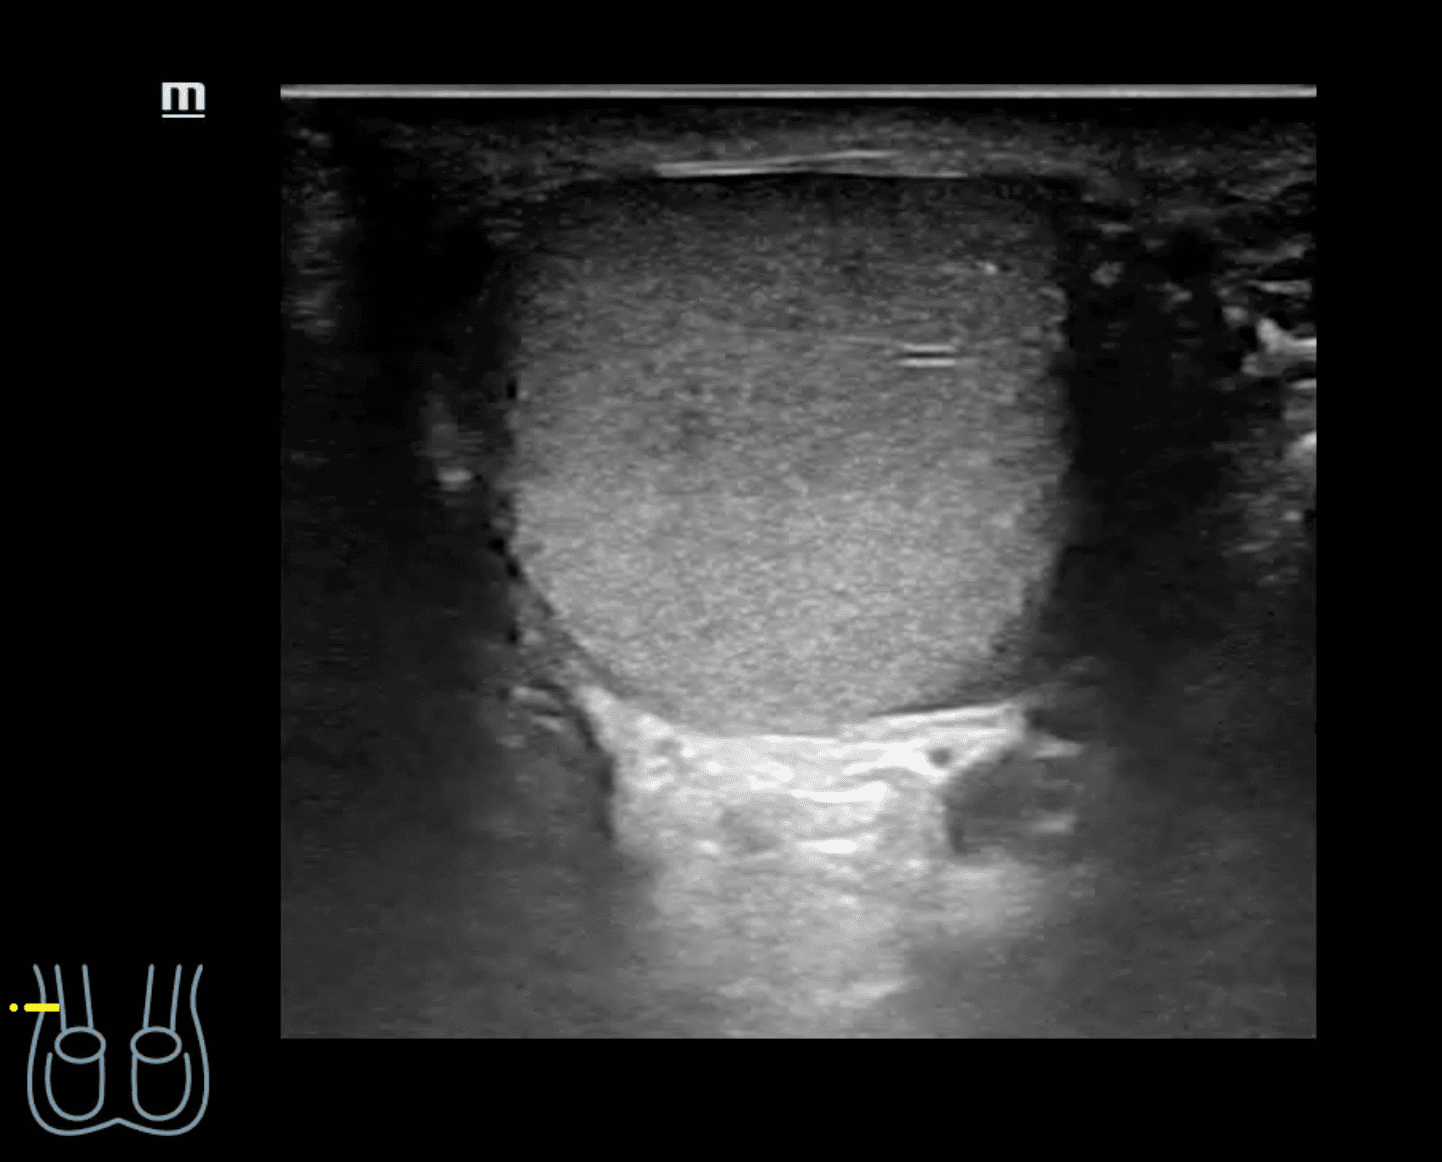

A nivel de escroto derecho, se observa imagen heterogénea con contenido intestinal compatible con hernia inguino-escrotal derecha. Testículos de aspecto normal.

Hernia inguino-escrotal derecha reductible dolorosa, no complicada.